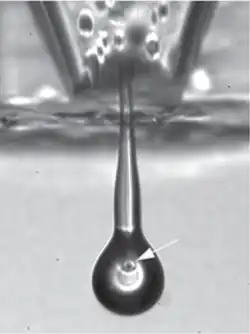

He is the inaugural Professor of Ophthalmology at the University of Cambridge and a specialist in the treatment of glaucoma. In 2013, Professor Martin's team tested a novel technique of bio-printing, using an ink jet to recreate layers of ganglion and glial cells from a rat's retina, a process that has been described as 'printing eyeballs'.

In 2009 he became Cambridge University's Professor of Ophthalmology. This was a new chair, sponsored by the Cambridge Eye Trust.[3] In 2013, he worked with Dr Barbara Lorber and others on the use of a piezoelectric inkjet nozzle to spray ganglion and glial cells from a rat retina.[4] The cells survived the process of deposition in layers and continued to grow in culture. With further development and testing, techniques like this could have clinical application for the repair of damaged retinas.[5][6]

- ^ Barbara Lorber; Wen-Kai Hsiao; Ian M Hutchings; Keith R Martin (17 December 2013), "Adult rat retinal ganglion cells and glia can be printed by piezoelectric inkjet printing", Biofabrication, 6 (1): 015001, doi:10.1088/1758-5082/6/1/015001, PMID 24345926